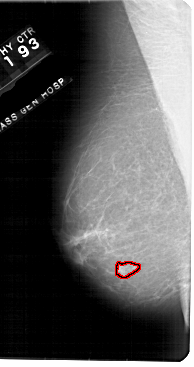

A_1948_1.LEFT_MLO

LEFT_MLO LINES 5491 PIXELS_PER_LINE 2896 BITS_PER_PIXEL 12 RESOLUTION 43.5 OVERLAY

FILE: A_1948_1.LEFT_MLO.OVERLAY

TOTAL_ABNORMALITIES 1

ABNORMALITY 1

LESION_TYPE MASS SHAPE IRREGULAR MARGINS ILL_DEFINED

ASSESSMENT 4

SUBTLETY 3

PATHOLOGY BENIGN

TOTAL_OUTLINES 1

BOUNDARY